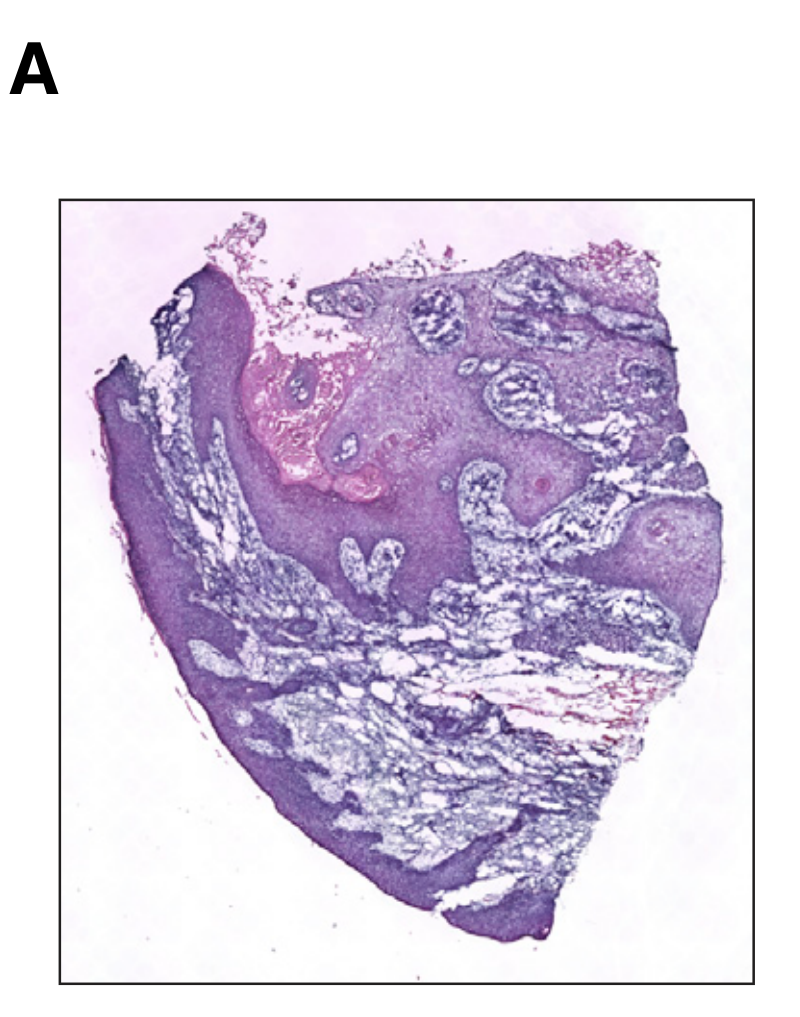

Wei R. et al. - 2022

Spatial charting of single-cell transcriptomes in tissues

Condition Dimension

N/A

Data Components

Biological Annotation

Data

Metadata

None

Modality

Sequencing-based

Resolution of observation

Functional tissue unit

Visualized Elements

Observation

Biological

Tissue

Abstraction

None

Chart Type

Histological image

Communicative/Contextualization

Annotation

Comparative Design

None

Layout

Spatial : Physical

Scalability Strategy

None (Item-level)

Where are tumor regions located within the spatial architecture of a tissue section?